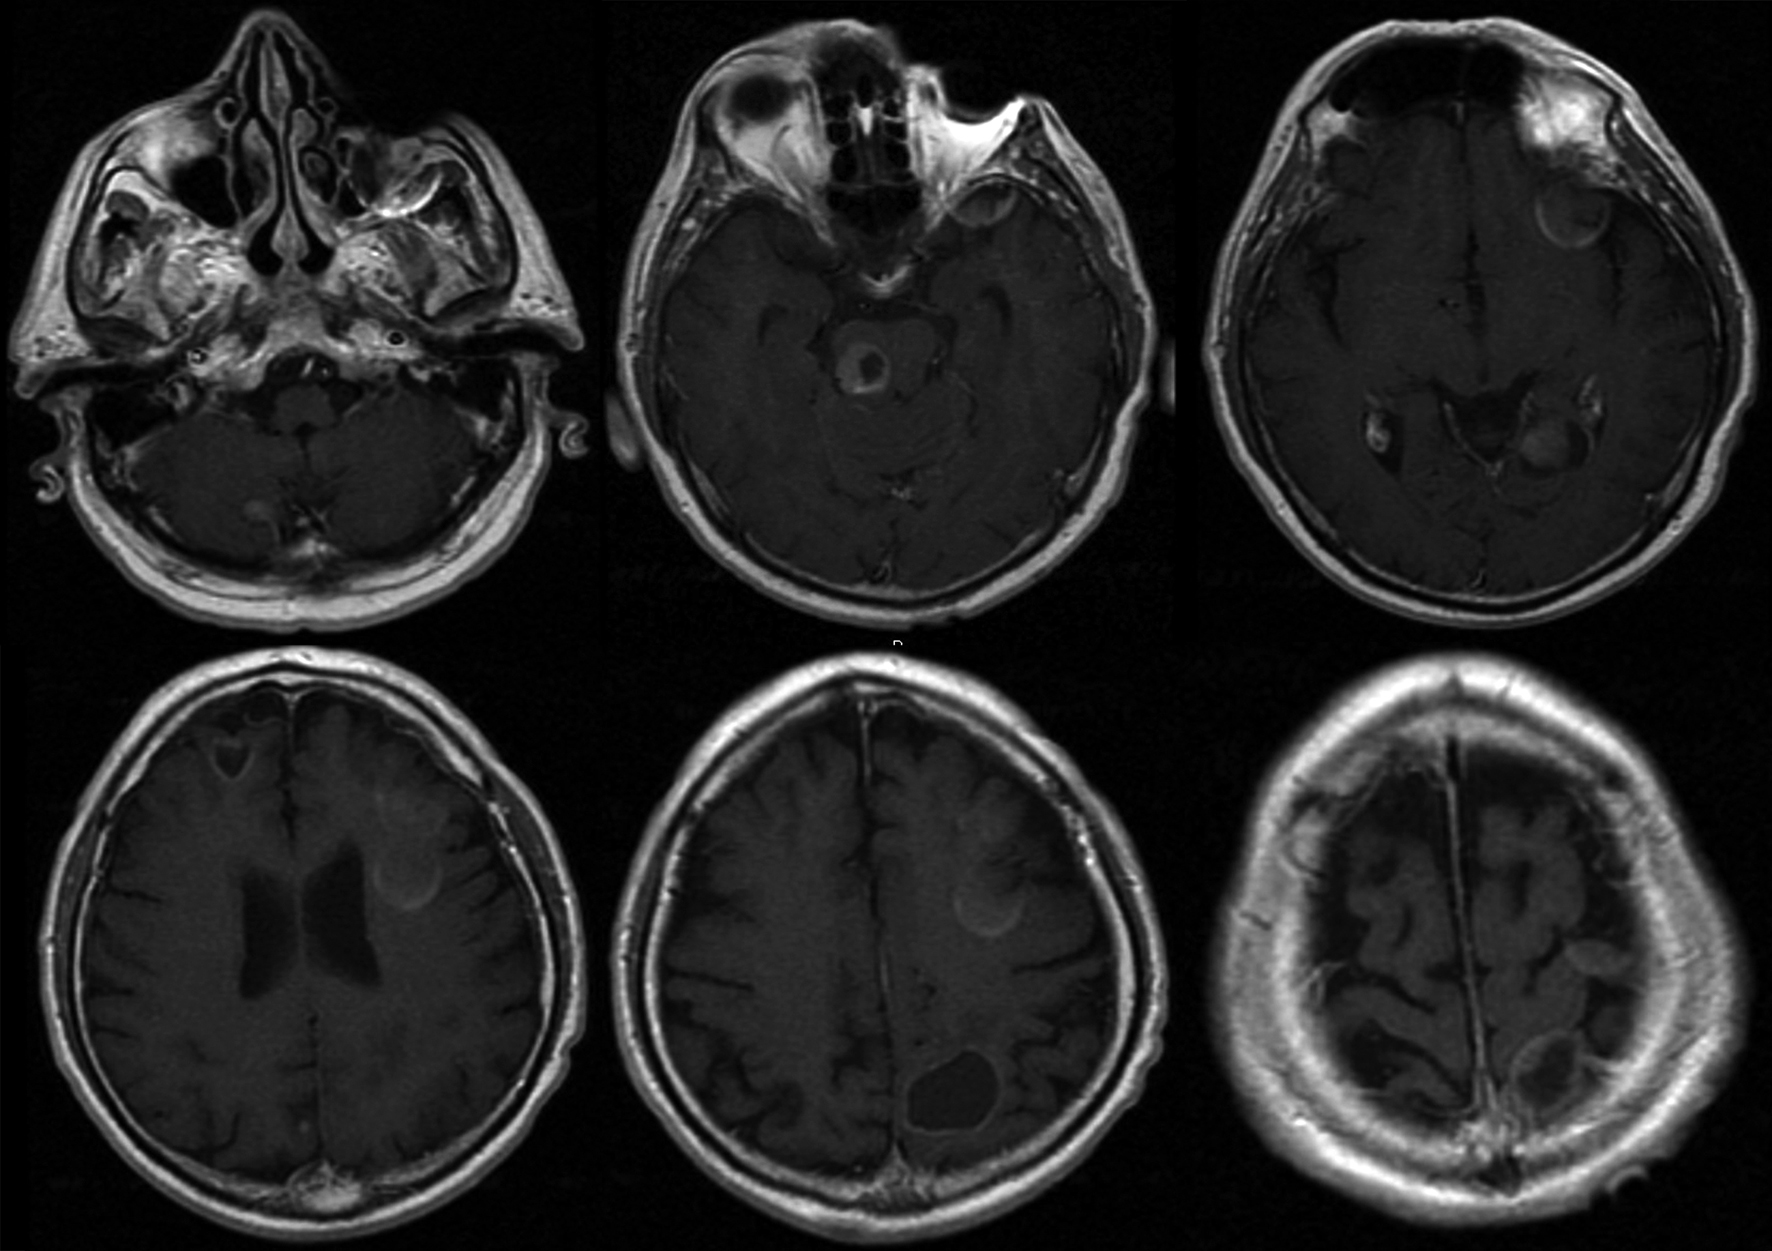

A man, 62 years old, was admitted at our Institute on October 2010 with a recent history of left limbs hypoesthesia and gait instability. Moreover, at the neurological examination a complete cerebellar syndrome associated to hypogeusia and weakness of left arm were found. A brain Magnetic Resonance (MR) with gadolinium showed six distinct cerebral cystic lesions (Fig. 1). A total-body Computed Tomography (CT) was performed with the evidence of multiple right lung nodules, a cystic right renal lesion and irregular prostate margins. The patient did not refer urinary impairment and the serum PSA value was 38.12 ng/dl. Multiple prostate biopsies were obtained and the histology showed adenocarcinoma and a positive immunohistochemical stain for PSA. The right frontal lesion was removed to achieve histologic characterization (Fig. 2). It was demonstrated to be a metastatic prostatic adenocarcinoma with a diffuse immunohistochemical stain for PSA and PSMA (Fig. 3). The patient underwent palliative radiation therapy.

![]() Click for large image | Figure 1. Brain MR with gadolinium showing the six distinct intraparenchymal lesions. |